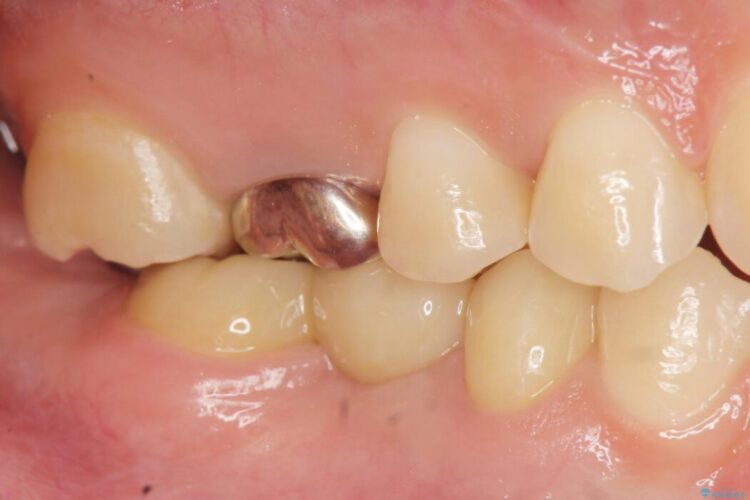

診査した結果、欠損した状態で長期間放置していたことが原因で最高峰の奥歯が欠けた部分に向かって傾斜してしまっていました。

この状態のままブリッジ治療へと進んでしまうと神経が露出する可能性が否定できないため、まずワイヤー装置による部分矯正で歯軸を通常位置へ戻してから補綴治療を行うこととしました。

本症例では、健康な歯を可及的に守るため神経の処置を避けた上で部分矯正を併用して行うことにより、安全に補綴治療(ブリッジ)ができました。